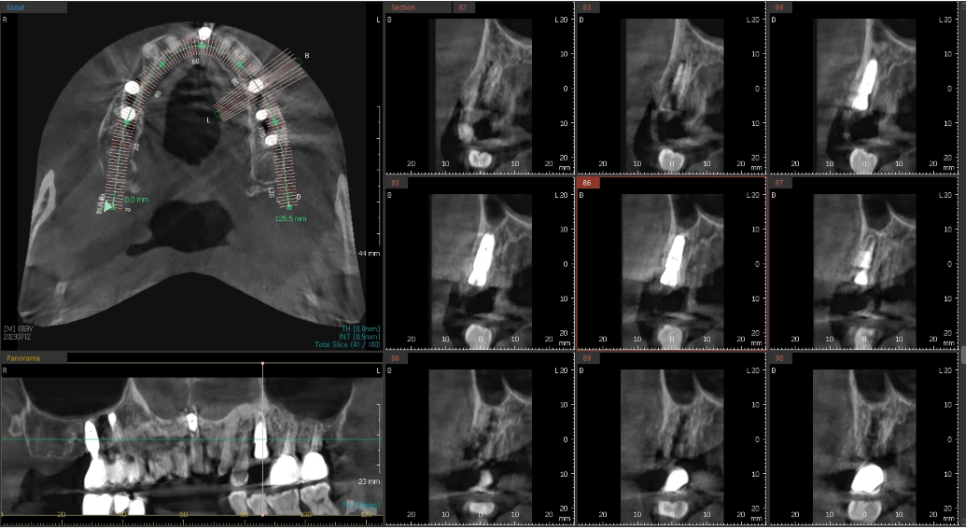

일단 파노라마 사진을 찍어 전체적인 상태를 체크해드렸습니다.

앞니쪽은 조금 더 자세하게 보기위해 치근단 엑스레이를 추가로 촬영하였습니다.

발치 후 염증으로 인해 대다수 소실된 뼈 부분을 보면

아주 얇고 경사가 심한 포인트라

임플란트를 심을 길을 내는 것도

아주아주 어려운 일입니다.

발치와 동시에 식립하는 임플란트는 정밀함을 요합니다.

앞니의 경우라면 더더욱 세심한 분석과 위치 선정이 중요하고

통상적으로 염증이 많은 부분을 깨끗하게 제거 한 뒤

뼈이식과 함께 임플란트를 하는

앞니 임플란트 술식은 매우 고난이도에 속합니다.

노란색으로 표시된 곡선의 움푹 들어간 부분이

실제로 수술시에 육안으로 잘 보이지 않기 때문에

손으로 만져보면서 조심스럽게 진행해야합니다.

또 너무 뒷쪽으로 식립하게 되는 경우

파란색 선 뒷쪽에 위치한 혀쪽의 설동맥과 가까워지게 되는데

설동맥을 건드린 경우는 대량의 출혈이 일어나게 됩니다.